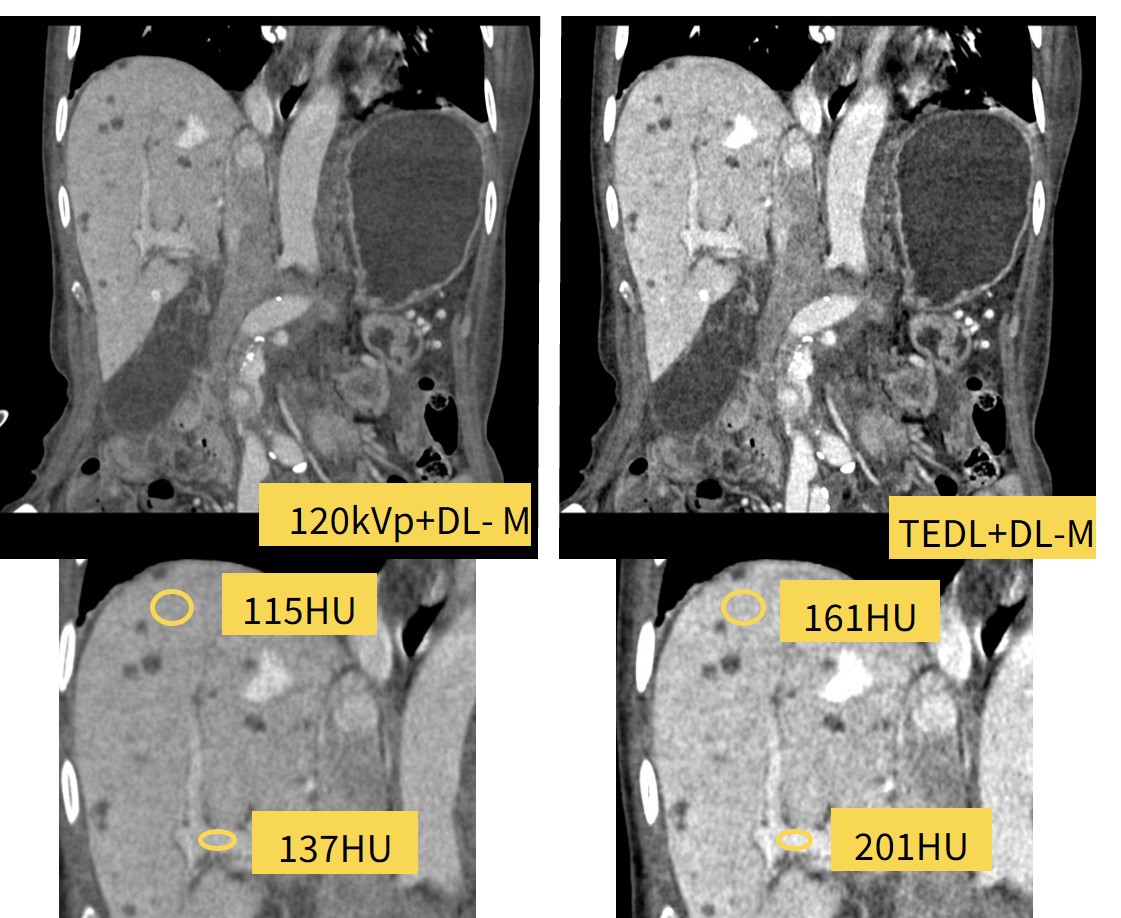

症例2)造影剤量を低減しTEDLが役に立った症例

中等度腎機能障害症例があり造影剤量を従来の7割にして撮影した症例になります。

120kVpと比較してTEDLではよりコントラストのついた画像になっており、肝実質と門脈のCT値を計測するとTEDLのほうがCT値の差が大きいことが確認できます。

撮影時に低管電圧にする設定の手間が不要で同等の画像を得ることが可能でした。

Fig6. 造影剤低減撮影でも、TEDLを使用することで撮影時の管電圧切り替えが不要